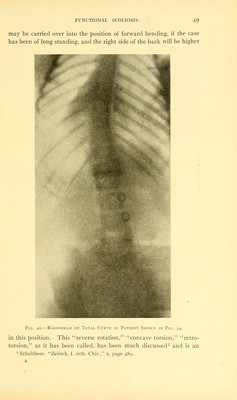

Lateral curvature of the spine and round shoulders / by Robert W. Lovett.

1912